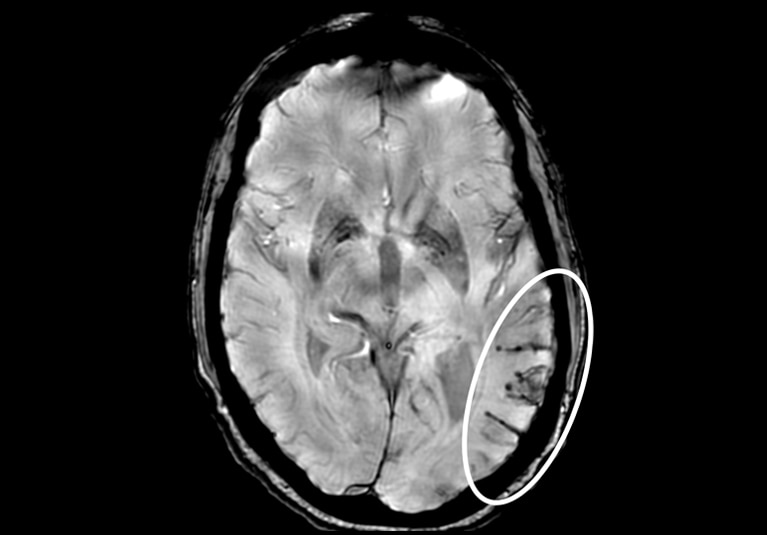

Severe ARIA-H Severe ARIA-H

Axial T2* gradient echo MRI demonstrates a large area of superficial siderosis and microhemorrhages in the left temporal region (white circle) — resulting in a diagnosis of amyloid-related imaging abnormalities-hemosiderin (ARIA-H).